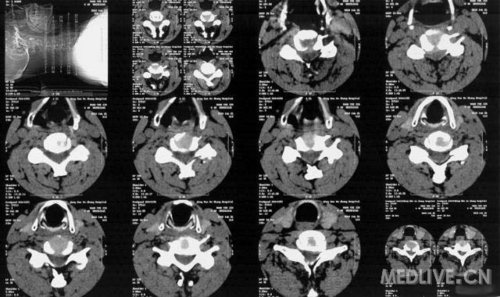

颈椎正侧位片

X线提示:颈椎后凸改变,颈椎3/4椎间隙变窄。